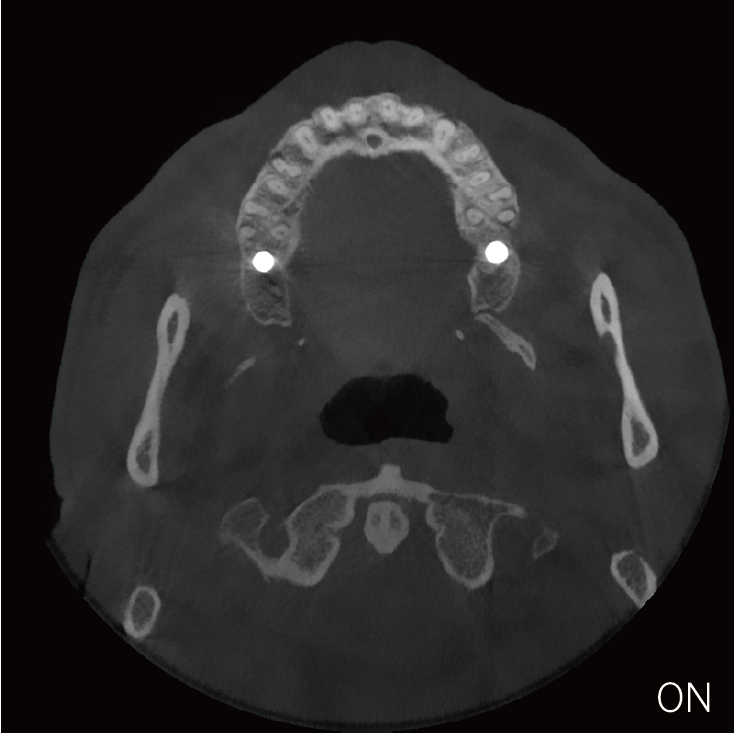

局部超清显示、 移动视野摄片

真人正侧位投影,实现CT成像区域无极可调

可根据临床需求任意调整成像区域大小实现局部超清三维显示

临床样片